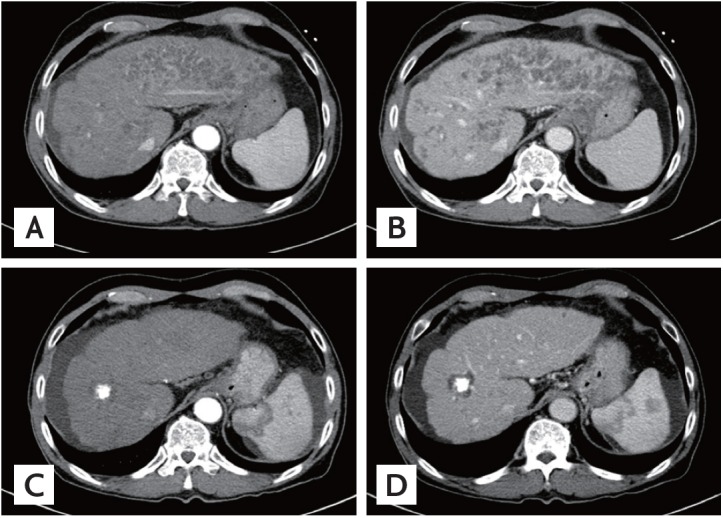

Serum liver enzyme levels increased abruptly the next day: AST, 2,604 U/L and ALT, 1,684 U/L. Tests for serum tumor markers revealed normal levels of α-fetoprotein (11.4 ng/mL) and protein induced by the absence of vitamin K or antagonist II (14 mAU/mL). Serological tests for hepatitis B and C were negative. A dynamic liver computed tomography (CT) scan was performed and arterial-phase CT scans showed multiple, clustered, irregularly marginated, hypoattenuating lesions scattered in the left hepatic lobe, the caudate lobe, and the periphery of the right lobe (Fig. 1A). The peripheral portions of these lesions were enhanced subtly on portal-venous (Fig. 1B) and delayed-phase images. Infarcted regenerative nodules were firstly suspected. However, we subsequently performed gadoxetate disodium-enhanced magnetic resonance imaging (MRI) because diffuse infiltrative HCC had not been completely excluded. MRI revealed multiple, clustered, nodular lesions with peripheral high signal intensities on T2-weighted images (Fig. 2A) and low signal intensities on T1-weighted images (Fig. 2B). The center portion of these lesions remained at low signal intensity; however, the peripheral portion was rim-enhanced during the arterial, portal, and delayed phases. These lesions showed low signal intensities with fuzzy margins during the hepatobiliary phase (Fig. 2C-2F). Furthermore, a 1-cm nodule with arterial enhancement and rapid washout was newly noted. This lesion was missed on the initial dynamic CT examination. Hepatic angiography showed nodular hypervascular tumor staining, corresponding to the MRI. TACE followed by radiofrequency ablation resulted in a complete response. Most of the lesions other than the newly detected HCC were found to be resolved on a 2-month follow-up CT scan (Fig. 1C and 1D).

Figure 1.

(A) An arterial-phase computed tomography (CT) image showing multiple, clustered, hypoattenuating nodules with peripheral rim enhancement in the left hepatic lobe, the caudate lobe, and the periphery of the right lobe. (B) A portal venous-phase CT image also showing multiple, clustered, hypoattenuating nodules with peripheral rim enhancement. The follow-up CT (C, arterial phase; D, portal phase) scan acquired 2 months later showing that the multiple hypoattenuating lesions have resolved. A lipiodol-laden hepatocellular carcinoma surrounded by non-enhancing ablation zone is also noted.